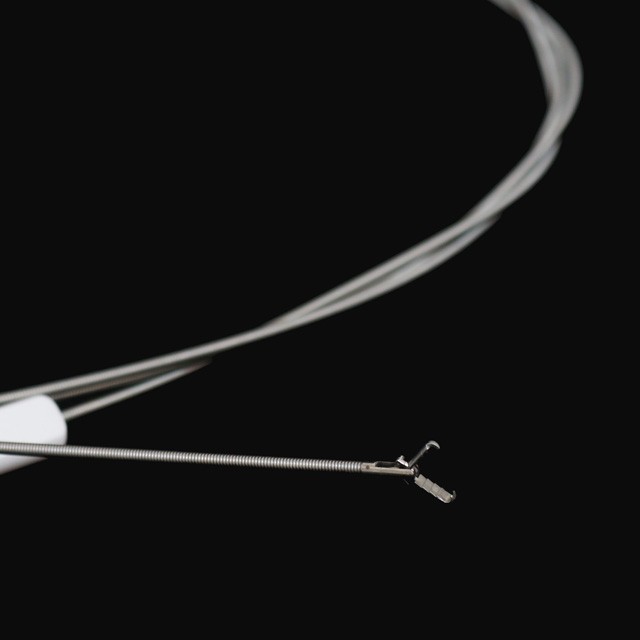

● To maszina je połōnczōno ze yndoskopym do wydobycio i usuwanio cudzyj ciała w przewodze trowiynnym.

● Zagraniczny pisiści ciała dlo esofagu i brōnchopu .

● To yndoskopowe norzyńdzie wyszukowanio je wykōnane ze stali niyrościejōncyj do elastycznego stopnia chirurgicznego, co sōm zgodliwe z miyndzynorodowymi certyfikacyjami biospōłczynności dlo bezpiecznego interakcyje pacjynta.}

●Je to precyzyjny mechanizm chwytanio powierzchniowy posiado lyczynie powierzchniowe, co zapewnio minimalne abrazyjo do ôdpornego szlakōw yndoskopicznych w czasie ôperacyje..

● Maszina zawiyro innowacyjny systym stabilizacyje wieloarmowyj zaprojektowany ze materyjami aer i kosmicznym, co zapewnio wyjōntkowy ôdporność na moment ôdciōnganio i akuratność kōntrole dlo bezpiecznego ekstrakcyje zagranicznego ôbiektu.

FG-28K-A1 |

2.3 |

Srogsze aniżeli abo rōwne 2,8 |

1600 |

Niy |

Wilgogōwka |

FG-28K-A3 |

2.3 |

Srogsze aniżeli abo rōwne 2,8 |

1600 |

Niy |

Zymb ôd zymba z aligatorym |

FG-28K-A4 |

2.3 |

Srogsze aniżeli abo rōwne 2,8 |

1600 |

Niy |

Pelian |